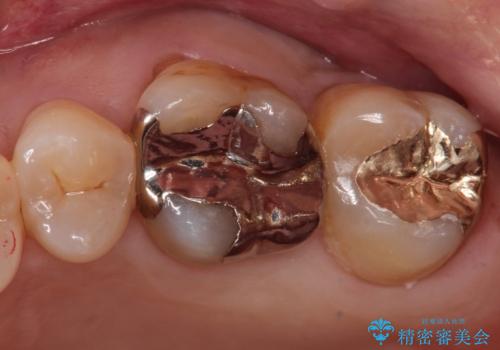

銀の詰め物が外れた。プラチナゴールドインレー

適合の良い修復を希望されましたので、プラチナゴールドインレーにて治療を行っております。

PGA(プラチナゴールド)インレーは適合もよく、壊れるリスクも極めて少ない修復です。